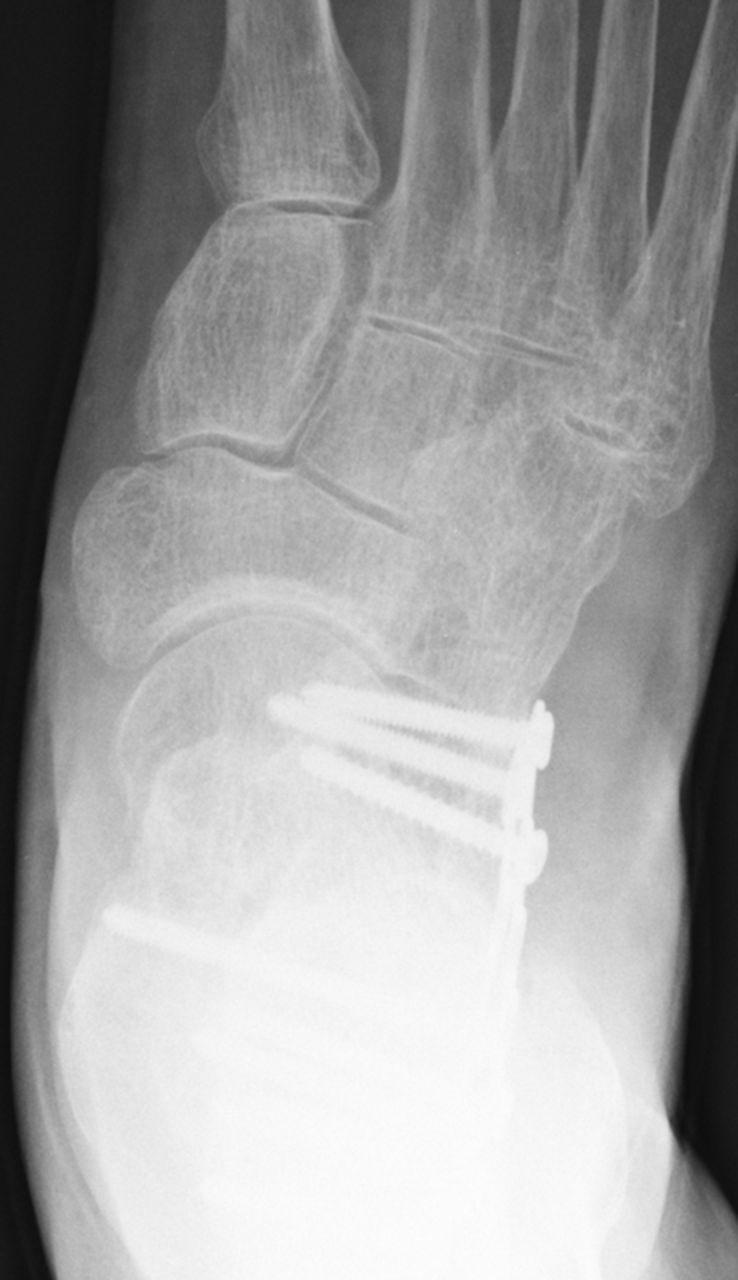

STEP 4 APPLY LAG FIXATION AND A LATERAL NEUTRALIZATION PLATE: Use a traditional nonlocking plate and be sure that at least one lag screw achieves purchase.

RESULTS & PREOP/POSTOP IMAGES: ORIF is a viable treatment option for displaced intra-articular calcaneal fractures without contraindication for older patients.

步骤4应用拉力固定和外侧中和钢板:使用传统非锁定钢板,确保至少有一枚拉力螺钉固定。

结果与术前/术后影像:对于无禁忌证的老年患者,切开复位内固定术是治疗关节内移位跟骨骨折的可行选择。